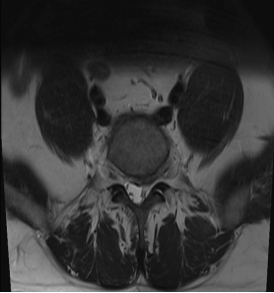

如果说UBE技术是脊柱治疗的“精准镜手”,那么3D打印技术就是定制化治疗的“私人裁缝”。针对每一位脊柱疾病患者的个体差异,医生通过高精度CT扫描,获取患者脊柱的三维立体数据,利用3D打印技术1:1还原脊柱的解剖结构——从椎体形态、椎间盘位置,到神经走行、病变范围,都能精准复刻,形成专属的脊柱模型。基于此模型,医生术前可以进行精准规划:模拟手术路径、预判操作风险、选择适配的内固定器械,甚至打印定制化的椎间融合器、内固定支架,确保手术操作“有的放矢”,贴合患者的个体解剖特征,避免传统手术中“凭经验操作”的不确定性,让脊柱治疗从“标准化”走向“个性化”,极大提升了手术的精准度与安全性。